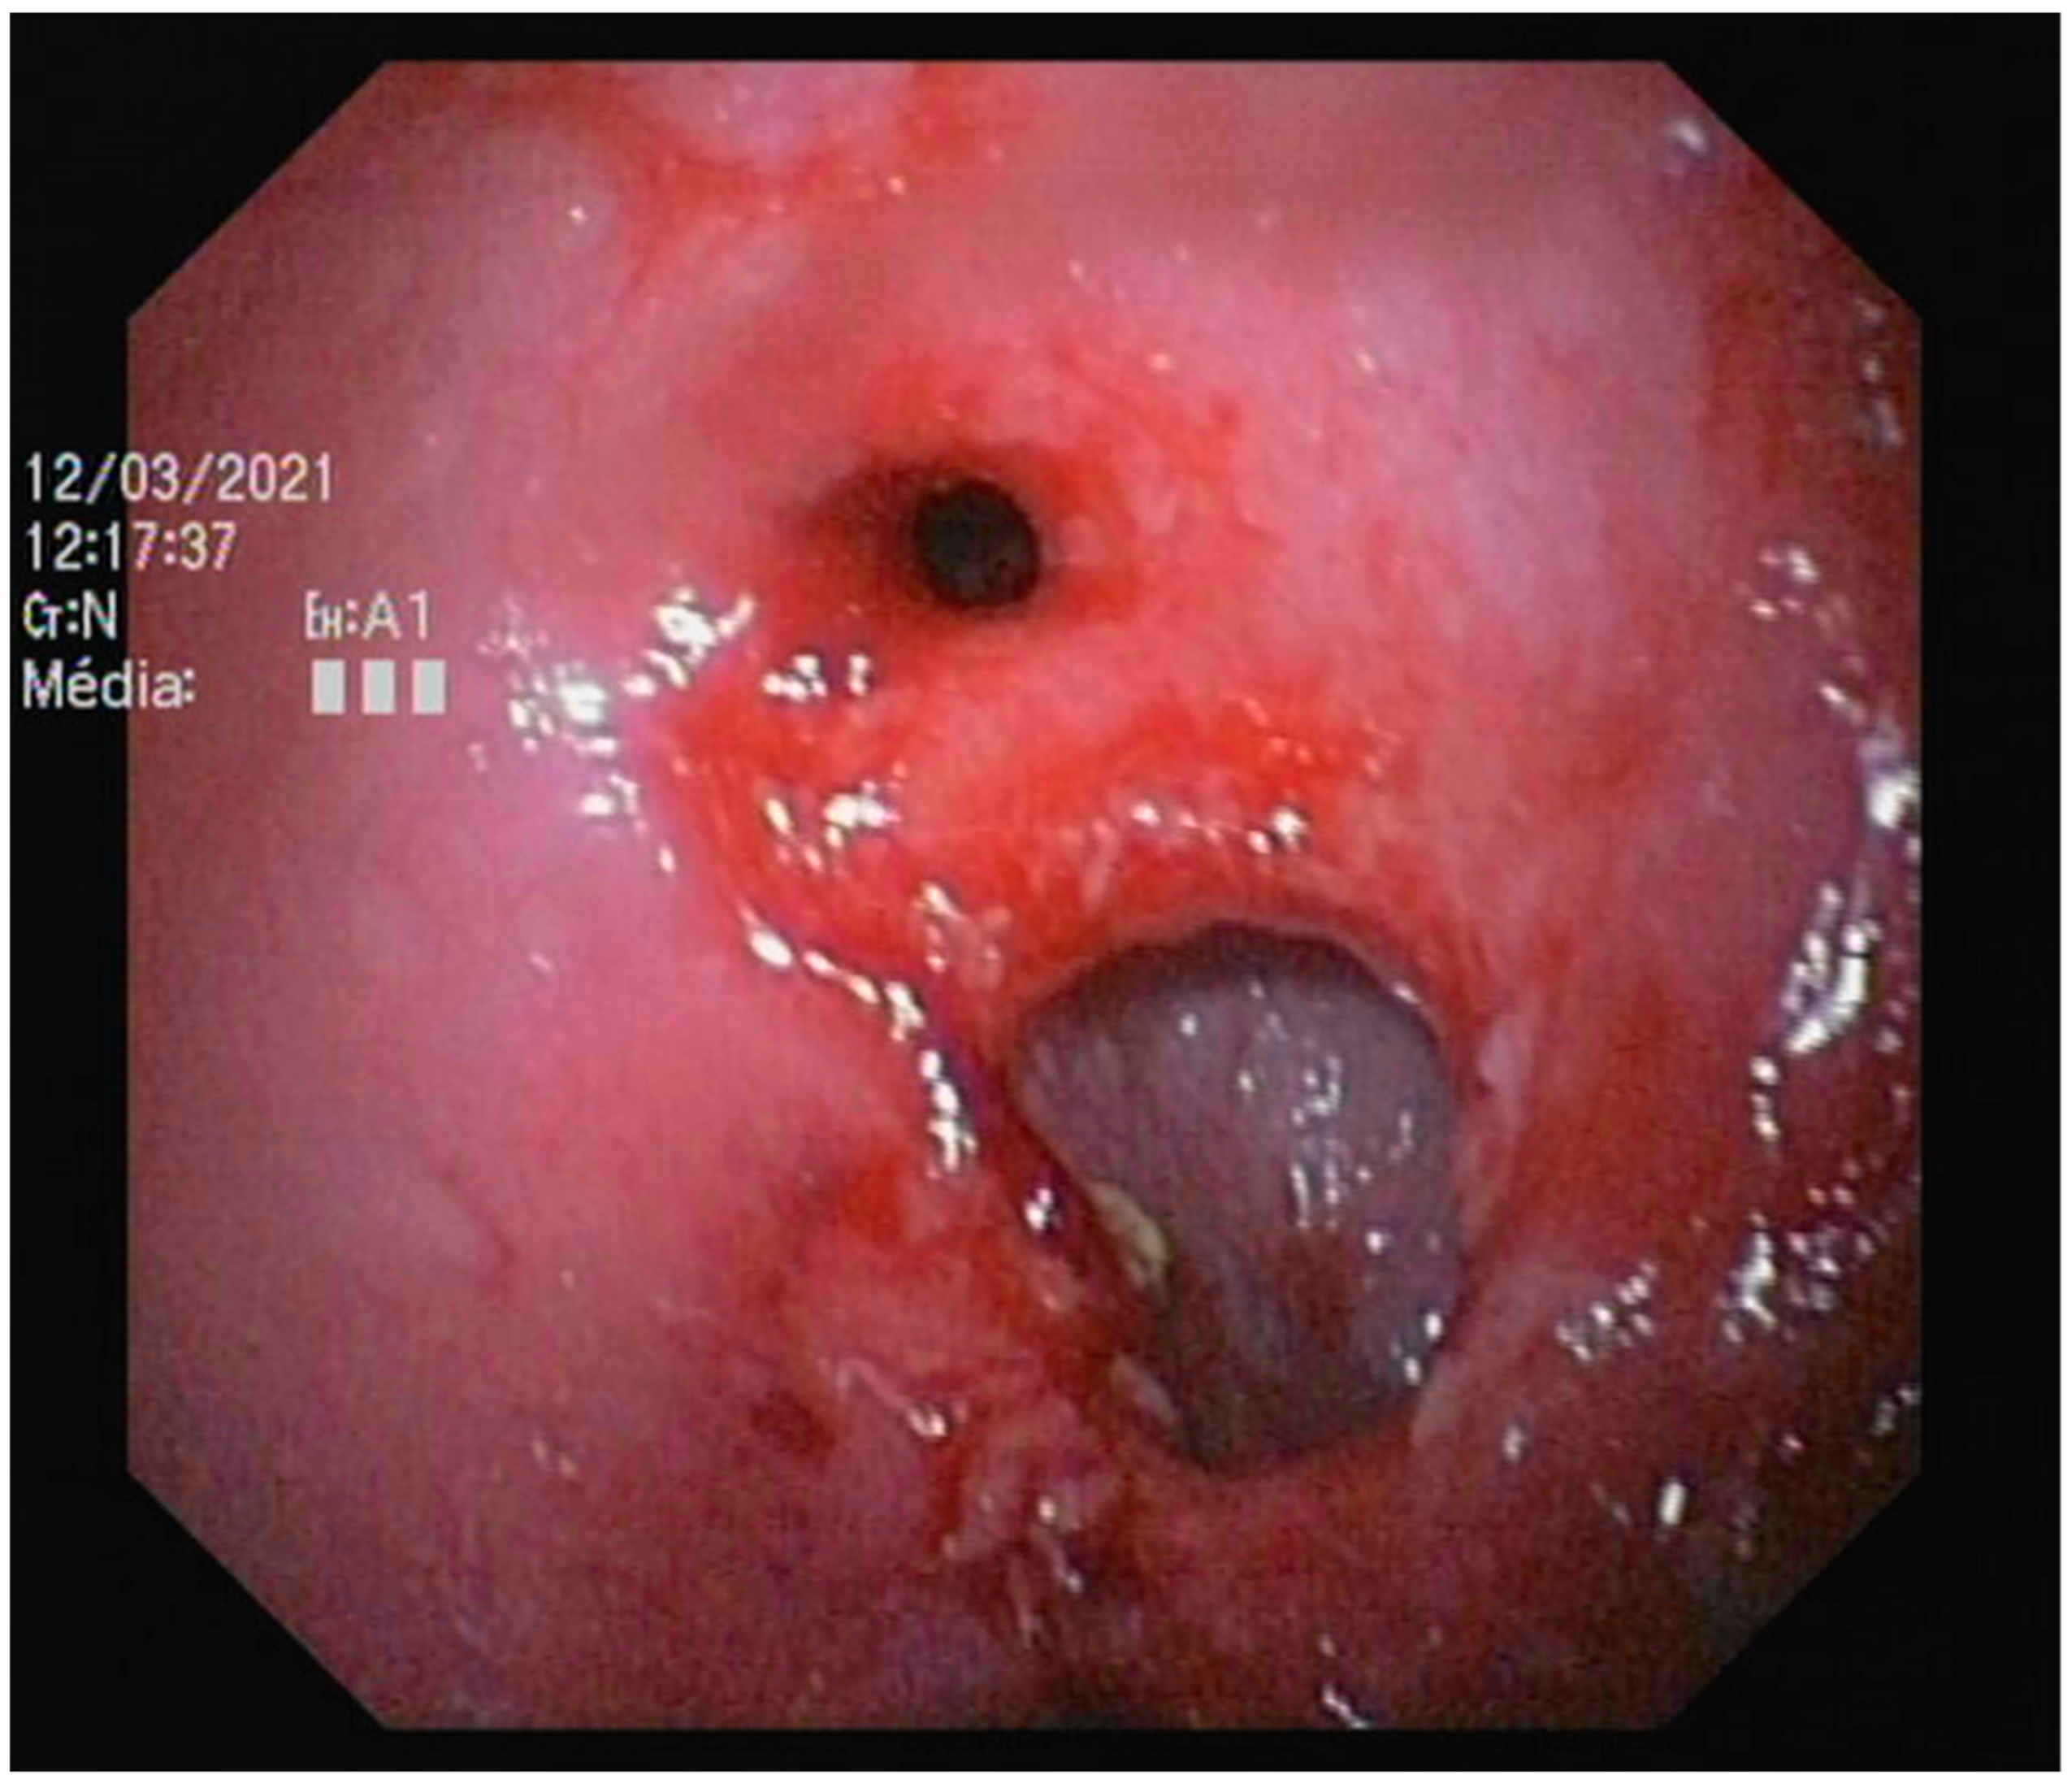

3.2.4. Endoscopic Findings